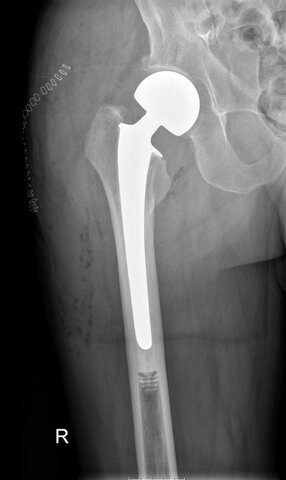

• Desarrollo de prótesis parciales de cadera

Desarrollo de prótesis parciales de cadera

Un cirujano de Boston, Marius Smith-Petersen desarrolla un dispositivo de vidrio destinado a la aplicación en prótesis parciales de cadera y clavos para la fijación de huesos. Usó una membrana reactiva similar a la sinovial que descubrió que se había desarrollado alrededor de un trozo de vidrio que había quitado de la espalda de un trabajador, que había estado incrustado allí durante un año.

• Avance en implantes totales de cadera

Avance en implantes totales de cadera

Se produce un hito que pasará a ser el más importante dentro de la historia de los implantes de cadera: el cirujano ortopedista inglés Sir John Charnley comienza un estudio sistemático de reemplazos totales de cadera con bajo coeficiente de fricción, siendo el primero en introducir al polímero Teflón como integrante del reemplazo de cadera y al polimetilmetacrilato como cemento para huesos.